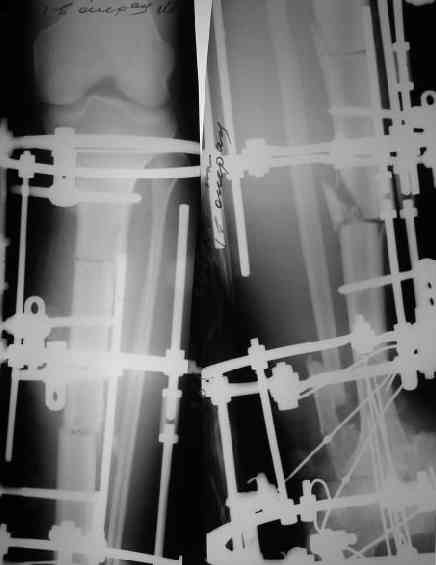

Снимки в приложении.

Да, при удалении таранной кости происходит гофрирование тканей. В данном случае есть еще и дублирование концов малоберцовой кости, которое должно устраниться при дистракции.